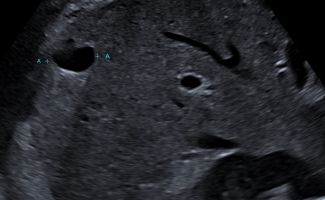

Ποιες παθολογίες εντοπίζονται με το Υπερηχογράφημα Κάτω Κοιλίας;

Το Yπερηχογράφημα Kάτω Kοιλίας αξιολογεί την ουροδόχο κύστη και τα έσω γεννητικά όργανα. Η πλήρωση της ουροδόχου κύστεως είναι απαραίτητη για τη διερεύνηση παθολογιών όπως:

- Λιθίαση

- Τοιχωματικές βλάβες

- Συμπαγείς βλάβες (όπως θηλώματα)

Στους άνδρες, αξιολογείται ο προστάτης, με μέτρηση των διαστάσεων και εκτίμηση του βαθμού υπερτροφίας και του κυστικού υπολείμματος μετά την ούρηση.

Στις γυναίκες, εξετάζονται η μήτρα και οι ωοθήκες, με μέτρηση του πάχους του ενδομητρίου και διερεύνηση για βλάβες όπως:

- Ινομυώματα

- Πολύποδες

Οι ωοθήκες ελέγχονται για την αξιολόγηση της μορφολογίας τους και πιθανών κύστεων ή συμπαγών βλαβών, καθώς και για τον έλεγχο σε περιπτώσεις υποψίας συνδρόμου πολυκυστικών ωοθηκών.